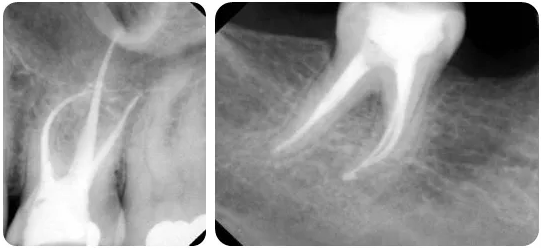

而最新的牙齿根管治疗技术:热牙胶充填,是目前临床上应用最为广泛的充填技术,其中热牙胶垂直加压充填技术的多步加热和加压改良为加热加压同时完成,让牙齿的功能恢复的更好更完美。

1.根管治疗并非都是一次完成的治疗,通常要经过开髓引流、牙髓失活、牙髓摘除、根管预备等多个步骤分3-5次完成,具体步骤则需要医生根据患者临床检查确定。